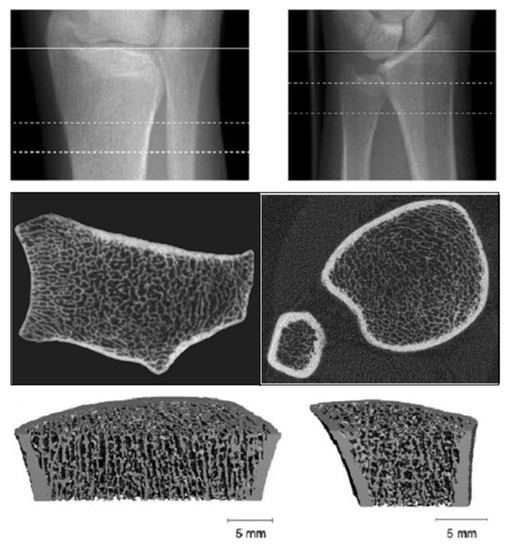

3.6. High Resolution-Peripheral Quantitative Computerized Tomography (HR-pQCT)